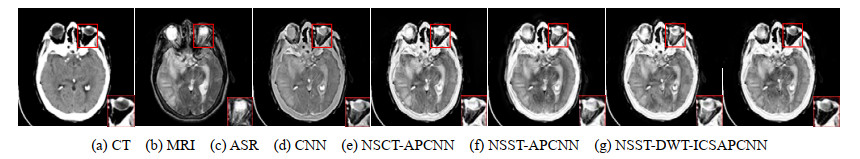

• 摘要: 为了增加融合图像的信息量,结合非下采样剪切波变换(Non-Subsampled Shearlet Transform, NSST)和离散小波变换(Discrete Wavelet Transform, DWT)的互补优势,提出了改进的多模态图像融合方法。采用NSST对两幅源图像进行多尺度、多方向的分解,得到相应的高频子带和低频子带;利用DWT将低频子带进一步分解为低频能量子带和低频细节子带,并利用最大值选择规则融合能量子带;采用改进连接强度的自适应脉冲耦合神经网络(Improved Connection Strength Adaptive Pulse Coupled Neural Network, ICSAPCNN)分别融合细节子带和高频子带,并对能量子带和细节子带进行DWT逆变换,得到融合的低频子带;采用NSST逆变换重构出细节信息丰富的融合图像。实验证明,提出的算法在主观视觉和客观评价方面均优于其他几种算法,且能同时适用于红外与可见光源图像、医学源图像的融合。

Abstract: To increase the information of the fused image, this paper proposes an improved multi-modality image fusion algorithm that combines the complementary advantages of the non-subsampled shearlet transform (NSST) and discrete wavelet transform (DWT). NSST was used to decompose the two source images in multiscale and multi-direction to obtain the corresponding high-frequency and low-frequency sub-bands. The low-frequency sub-bands were further decomposed into low-frequency energy sub-bands and low-frequency detail sub-bands by the DWT, and the low-frequency energy sub-bands were fused by the maximum selection rules. An adaptive pulse-coupled neural network with improved connection strength (ICSAPCNN) was used to fuse the detailed sub-bands and high-frequency sub-bands, and the energy sub-bands and detailed sub-bands were fused by inverse DWT to obtain the fused low-frequency sub-bands. The NSST inverse transform was used to reconstruct the fusion image with rich details. The experimental results verified that the proposed algorithm is superior to the other algorithms in both subjective vision and objective evaluation and can be applied to the fusion of both infrared and visible source images and medical source images.